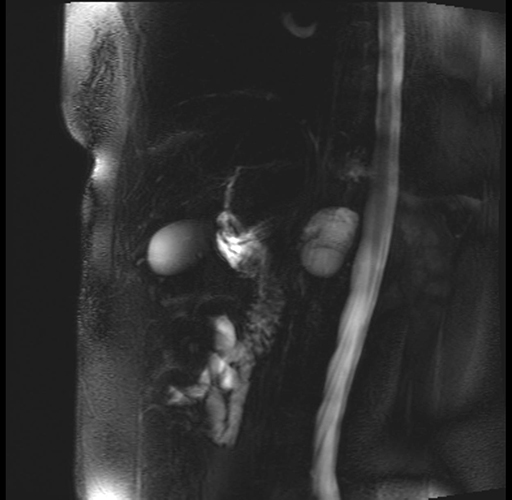

Imaging Analysis

Look through the patient's CT scan to identify any areas of concern for the necessary procedure.

Based on your CT findings, which issue(s) are present and would give reason for "planned slowing down moment(s)" in this case?

Considering a standard distal pancreatectomy procedure, what step(s) of the operation would you do differently in this case?